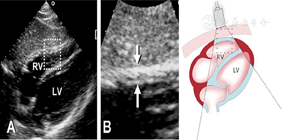

(1)胸骨旁左心室长轴切面(图1图2图3)

胸骨旁左心室长轴切面引导2a区M型超声心动图,显示收缩末期和舒张末期室间隔厚度、左心室内径和左心室后壁厚度测量方法

胸骨旁左心室长轴切面,显示二维超声心动图舒张末期左右心室壁厚度、室间隔厚度和左右心室内径测量方法

图3

胸骨旁左心室长轴切面,显示舒张末期主动脉瓣环内径、主动脉窦部内径和主动脉根部内径以及收缩末期左心房前后径测量方法,建议在窦管线上2 cm处测量主动脉根部内径,窦部内径测量应当避开右冠状动脉开口的漏斗部。左心室流出道前后径应在主动脉瓣下1 cm处测量。左心房测量应避开膨大的无冠窦窦壁和肺静脉开口